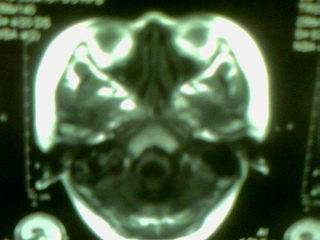

标题: MRI2125:女 45岁 头疼头晕3个月 [打印本页]

标题: MRI2125:女 45岁 头疼头晕3个月

1)考虑第四脑室脉络膜丛乳头状瘤,不排除室管膜瘤。2)阻塞性脑积水。

1)考虑第四脑室室管膜瘤,不排除脉络膜丛乳头状瘤。2)阻塞性脑积水。

第四脑室脉络丛乳头状瘤,典型!

考虑第四脑室室管膜瘤,不排除脉络膜丛乳头状瘤。2)阻塞性脑积水